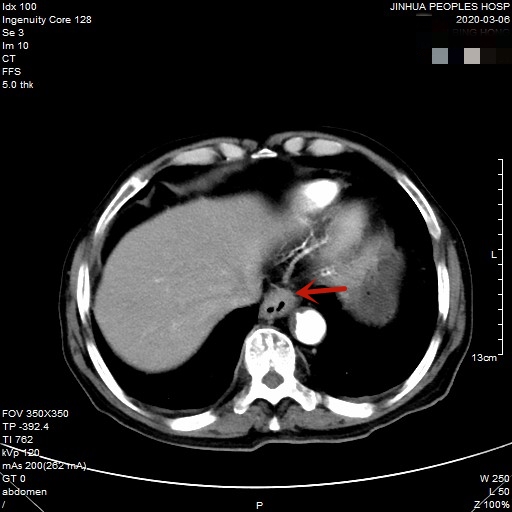

医生予以进一步检查CT增强发现肿瘤倒是没有明显侵犯周围脏器或结构,请我去会诊后,仔细阅片,发现从影像上看还是能够根治性切除的。所以转来胸外科拟进一步行手术治疗。下面是其CT增强的图像:

以上图片红色箭头所指处为贲门部肿瘤